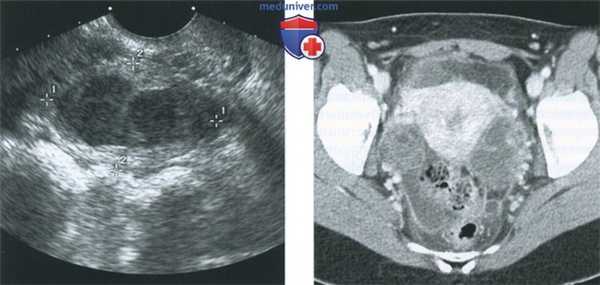

(Слева) Трансвагинальная уль трасонография в продольной плоскости; визуализируется расширенная болезненная фаллопиева труба, содержащая низкоуровневые эхосигналы и неполную перегородку. Такие признаки характерны для пиосальпинкса.

(Справа) MPT, Т2, TSE, сагиттальный срез у этой же пациентки; определяется уровень детрита в пиосальпинксе. Бесчисленные крупные фиброиды было трудно оценить при ультрасонографии.

(Слева) Трансвагинальная ультрасонография матки в коронарной плоскости у пациентки с воспалительными заболеваниями органов малого таза (ВЗОМТ); определяется жидкость эндометрия, что указывает на эндометрит.

(Справа) Трансвагинальная цветовая допплерография в коронарной плоскости: многокамерный тубоовариальный абсцесс с детритом и окружающей гиперемией.